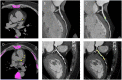

Methods: Computed tomography coronary angiography (CTCA) was performed in a group of 20 diabetic patients with CAD (DM+CAD+), 20 non-diabetic with CAD (DM-CAD+), 10 diabetic non-CAD patients (DM+CAD-), and 20 non-diabetic healthy subjects (HS). Imaging quantitative parameters such as calcium score (Cascore), calcified plaque volume (CPV), non-calcified plaque volume (NCPV), total plaque volume (TPV), remodeling index (RI), and plaque burden were extracted for each CAD subject. Moreover, the expression levels of superoxide dismutase 2 (SOD2) and liver X receptor alpha (LXRα) genes were analyzed in the peripheral blood mononuclear cells, whereas hyaluronan (HA) concentrations were evaluated in the plasma of each subject.